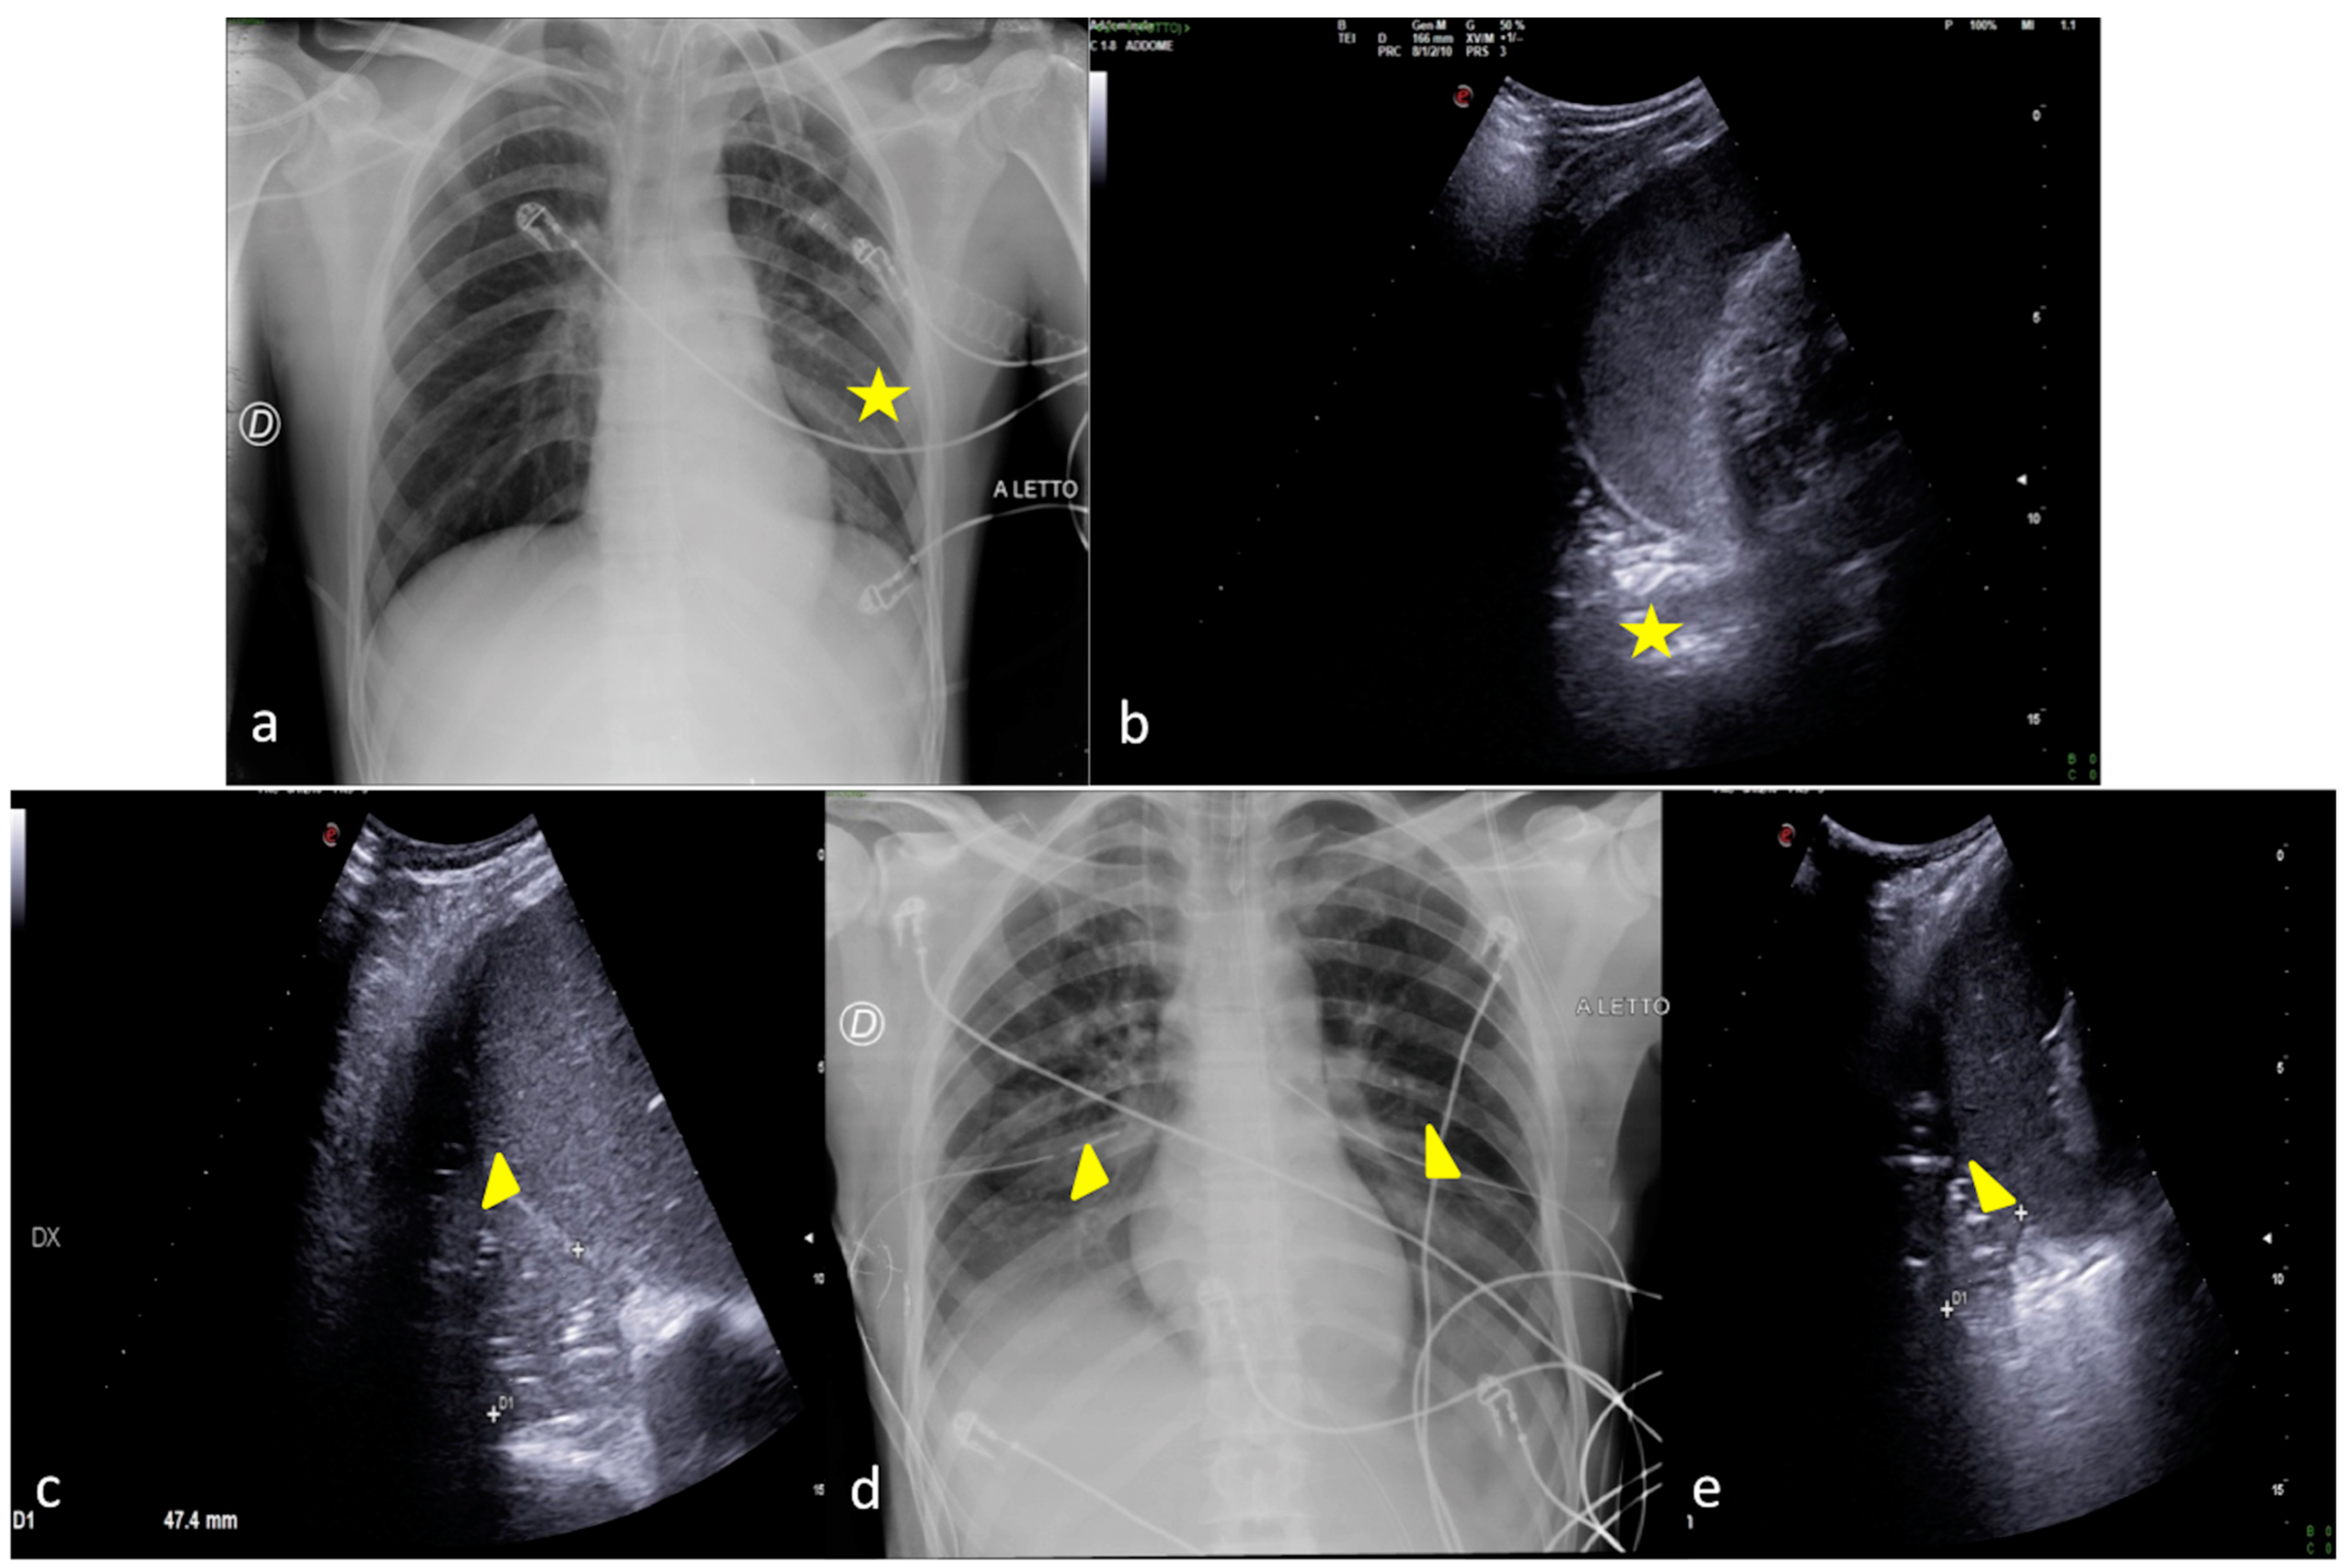

2.3. Pleural Effusion

- Shao, R.-J.; Du, M.-J.; Xie, J.-T. Use of lung ultrasound for the diagnosis and treatment of pleural effusion. Eur. Rev. Med. Pharmacol. Sci. 2022, 26, 8771–8776. [Google Scholar] [CrossRef]

- Brogi, E.; Gargani, L.; Bignami, E.; Barbariol, F.; Marra, A.; Forfori, F.; Vetrugno, L. Thoracic ultrasound for pleural effusion in the intensive care unit: A narrative review from diagnosis to treatment. Crit. Care 2017, 21, 325. [Google Scholar] [CrossRef]

- Kitazono, M.T.; Lau, C.T.; Parada, A.N.; Renjen, P.; Miller, W.T. Differentiation of Pleural Effusions From Parenchymal Opacities: Accuracy of Bedside Chest Radiography. Am. J. Roentgenol. 2010, 194, 407–412. [Google Scholar] [CrossRef]

| Pleural Effusion | Supine chest radiography may reveal abnormality when the amount of fluid reaches 175–525 mL, which is higher than that for upright chest radiography. | US may detect 5–20 mL of pleural fluid with an overall sensitivity of 89–100% and specificity of 96–100%. |